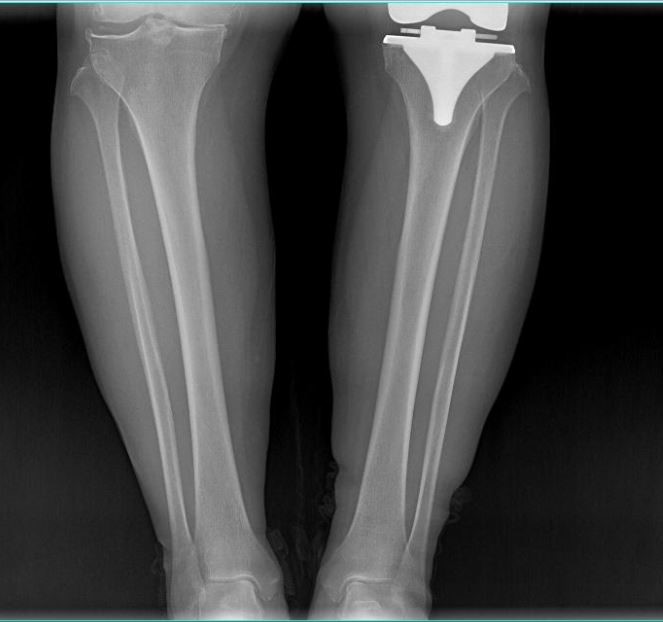

女 65岁

左侧膝关节置换术后

左侧膝关节置换术后复查

通过全景拼接图像可以清晰显示双下肢对比情况,为术后评估提供更多影像学资料。